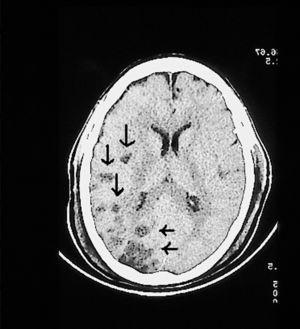

Mujer de 65 años, que ingresó en el Servicio de Medicina Intensiva diagnosticada de meningitis por Streptococcus pyogenes secundaria a otitis supurada y mastoiditis izquierda. Antibioticoterapia según antibiograma. Se realizó tomografía axial computarizada (TAC) por deterioro del nivel de conciencia compatible con meningitis. Tres días después presentó status convulsivo que fue tratado con inducción de coma barbitúrico; se realizó nueva TAC (fig. 1) sugerente de encefalitis necrotizante corticosubcortical temporooccipital izquierda secundaria a vasculitis o a trombosis venosa cortical. El octavo día de ingreso presentó anisocoria, por lo que se le realizó resonancia magnética (RM) (fig. 2) que demostró hematoma frontal izquierdo espontáneo que requirió drenaje quirúrgico. La enferma estaba recibiendo 80 mg/24 h de heparina sódica en perfusión continua por HDFVVC, con tiempos de cefalina en el rango normal. La paciente presentó mala evolución, falleciendo a los 20 días del ingreso tras limitación del esfuerzo terapéutico en el contexto de shock séptico refractario (cultivos necrópsicos en Pseudomonas aeruginosa en pulmón y serosa pleural) y fallo multiorgánico.

Figura 1